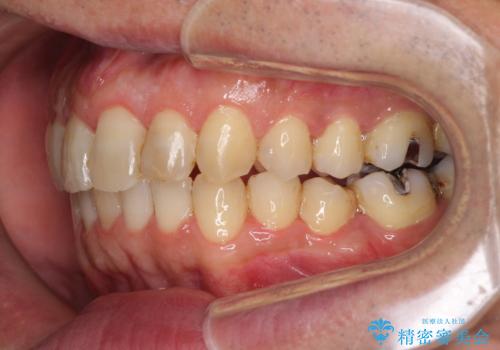

- 外に飛び出した側方の歯と、前歯のデコボコを気にして来院された患者様です。

IPR(歯と歯の間を削る)によってデコボコが解消するように設計し、インビザラインにより治療を行うこととしました。

治療途中で1年半以上通院されない時期があったため、後戻りが生じたことで治療期間が長くなってしまいました。

親知らずを抜去したことで、下顎のデコボコがきれいに解消されました。